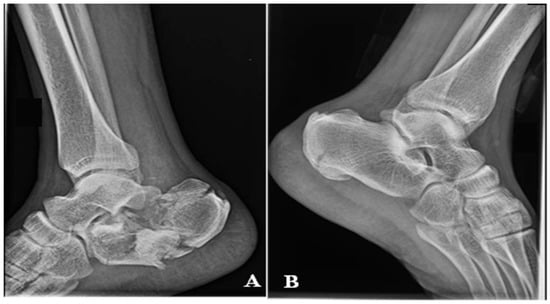

Figure 10. X-ray view after ORIF.

After debridement of the necrotic area, the soft tissue defect was about 6 cm × 7 cm. Figure 9. The fracture was reduced and fixed through the ORIF method with two canulated screws. Figure 10.